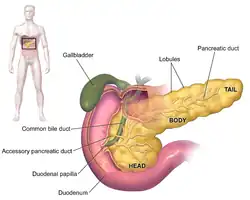

O cancro (português europeu) ou câncer (português brasileiro) do pâncreas surge quando as células do pâncreas, um órgão glandular atrás do estômago, se começam a multiplicar de forma descontrolada e formam um tumor. Estas células cancerígenas têm a capacidade de invadir outras partes do corpo.[10] Existem diversos tipos de cancro do pâncreas. O mais comum, adenocarcinoma pancreático, corresponde a aproximadamente 85% dos casos e em muitas situações o termo "cancro do pâncreas" é usado para designar apenas este tipo. Estes adenocarcinomas começam-se a formar na parte do pâncreas que produz as enzimas digestivas. A partir destas células podem também surgir vários outros tipos de cancro, que no conjunto representam a maioria dos não-adenocarcinomas. Um a dois em cada 100 casos de cancro do pâncreas são tumores neuroendócrinos que se formam a partir das células do pâncreas produtoras de hormonas. Este tipo é geralmente menos agressivo que o adenocarcinoma pancreático.[2]

Os diversos tipos de cancro do pâncreas podem ser divididos em dois grupos genéricos. A grande maioria dos casos (99%) ocorre na parte do pâncreas que produz enzimas digestivas, denominada de componente exócrino. Embora existam vários subtipos de cancros pancreáticos exócrinos, o diagnóstico e tratamento é em grande parte idêntico. A pequena minoria de cancros que surge no tecido produtor de hormonas (endócrino) apresenta características clínicas diferentes. Ambos os grupos ocorrem principalmente (mas não de forma exclusiva) em pessoas com mais de 40 anos e são ligeiramente mais comuns em homens. No entanto, alguns subtipos mais raros ocorrem principalmente em mulheres ou crianças.[16][17]

O grupo exócrino é dominado pelo adenocarcinoma pancreático, também denominado "invasivo" ou "ductal", que é de longe o tipo mais comum e corresponde a cerca de 85% de todos os cancros pancreáticos.[2] Por outro lado, o tecido a partir do qual se forma, o epitélio ductal pancreático, representa apenas 10% do volume de células do pâncreas.[18] Este cancro tem origem nos ductos que transportam determinadas hormonas e enzimas para fora do pâncreas. Cerca de 60–70% dos adenocarcinomas ocorrem na cabeça do pâncreas (ver diagrama à direita).[2]

Os sintomas de adenocarcinoma pancreático geralmente não se manifestam durante as fases iniciais da doença e, individualmente, não são exclusivos da doença (inespecíficos).[11][3][27] Os sintomas no momento do diagnóstico variam de acordo com a localização do cancro no pâncreas, órgão que os anatomistas dividem em cabeça, pescoço, corpo e cauda. Cerca de 60–70% dos cancros pancreáticos localizam-se na cabeça do pâncreas.[2] O sintoma mais comum, qualquer que seja a localização, é a perda inexplicável de peso, que pode ser considerável. Os tumores na cabeça da glândula também provocam icterícia, dores abdominais, perda de apetite, urina escura e fezes de cor clara. Os tumores do corpo e da cauda do pâncreas geralmente também provocam dor. Uma parte significativa das pessoas diagnosticadas (entre 35 e 47%) também apresenta náuseas, vómitos e sensação de fraqueza.[27]